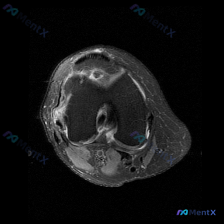

看到一份很有讨论价值的膝关节MRI病例,整理了影像发现和分析思路,和大家一起交流。 病例影像基本信息 这是一份膝盖MRI的轴位T2加权图像,扫描层面位于髌股关节滑车沟层面,可观察到以下明确异常: 1. 髌骨改变:髌骨后方关节软骨信号不均匀、局部T2高信号,软骨形态不规则、厚度变薄;髌骨边缘骨质可见高...